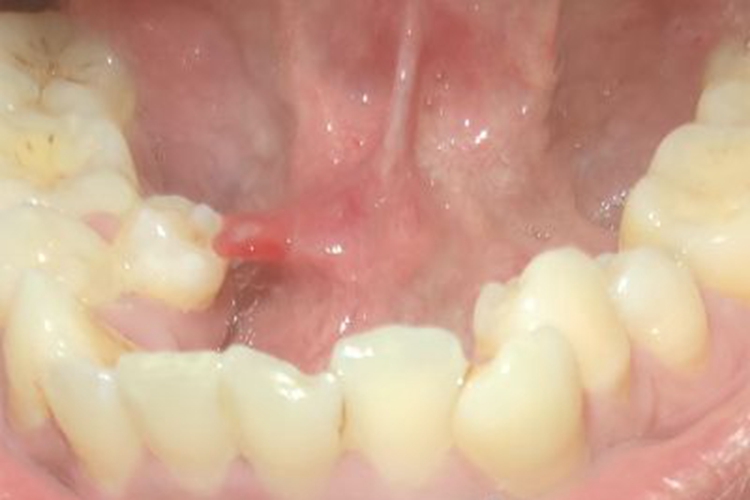

涎腺囊肿症状表现为舌头根部出现一个鲜红色的突起物,状似小肉赘,如绿豆大小,触摸时自觉柔软并且有轻微的波动感,无明显的不适。

涎腺囊肿可发生在腮腺、颌下腺及舌下腺区,涎腺导管因炎症或结石阻塞使腺体分泌物潴留所致,阻塞原因多系损伤,有时多次反复损伤,可形成瘢痕而阻塞排泄管。